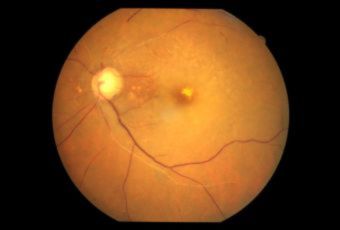

CENTRAL SEROUS RETINOPATHY (CSR) |

Smoke stack appearance

Ink blot appearance